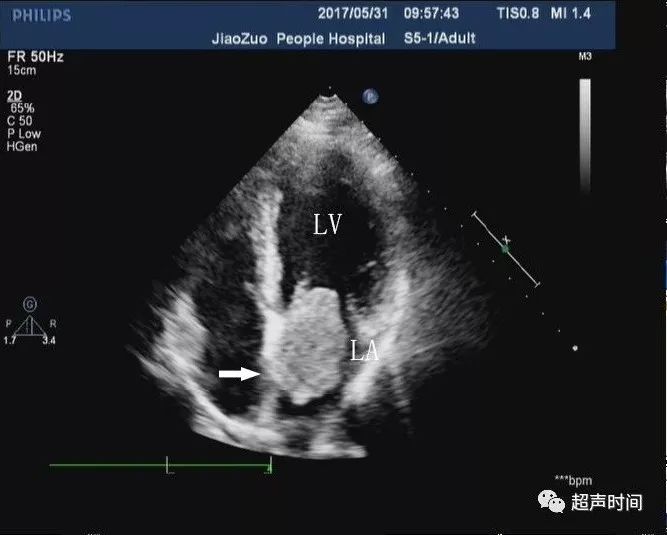

横纹肌瘤的超声心动图诊断及典型病例分享

左房黏液瘤有没有哪些知识点是你不知道的